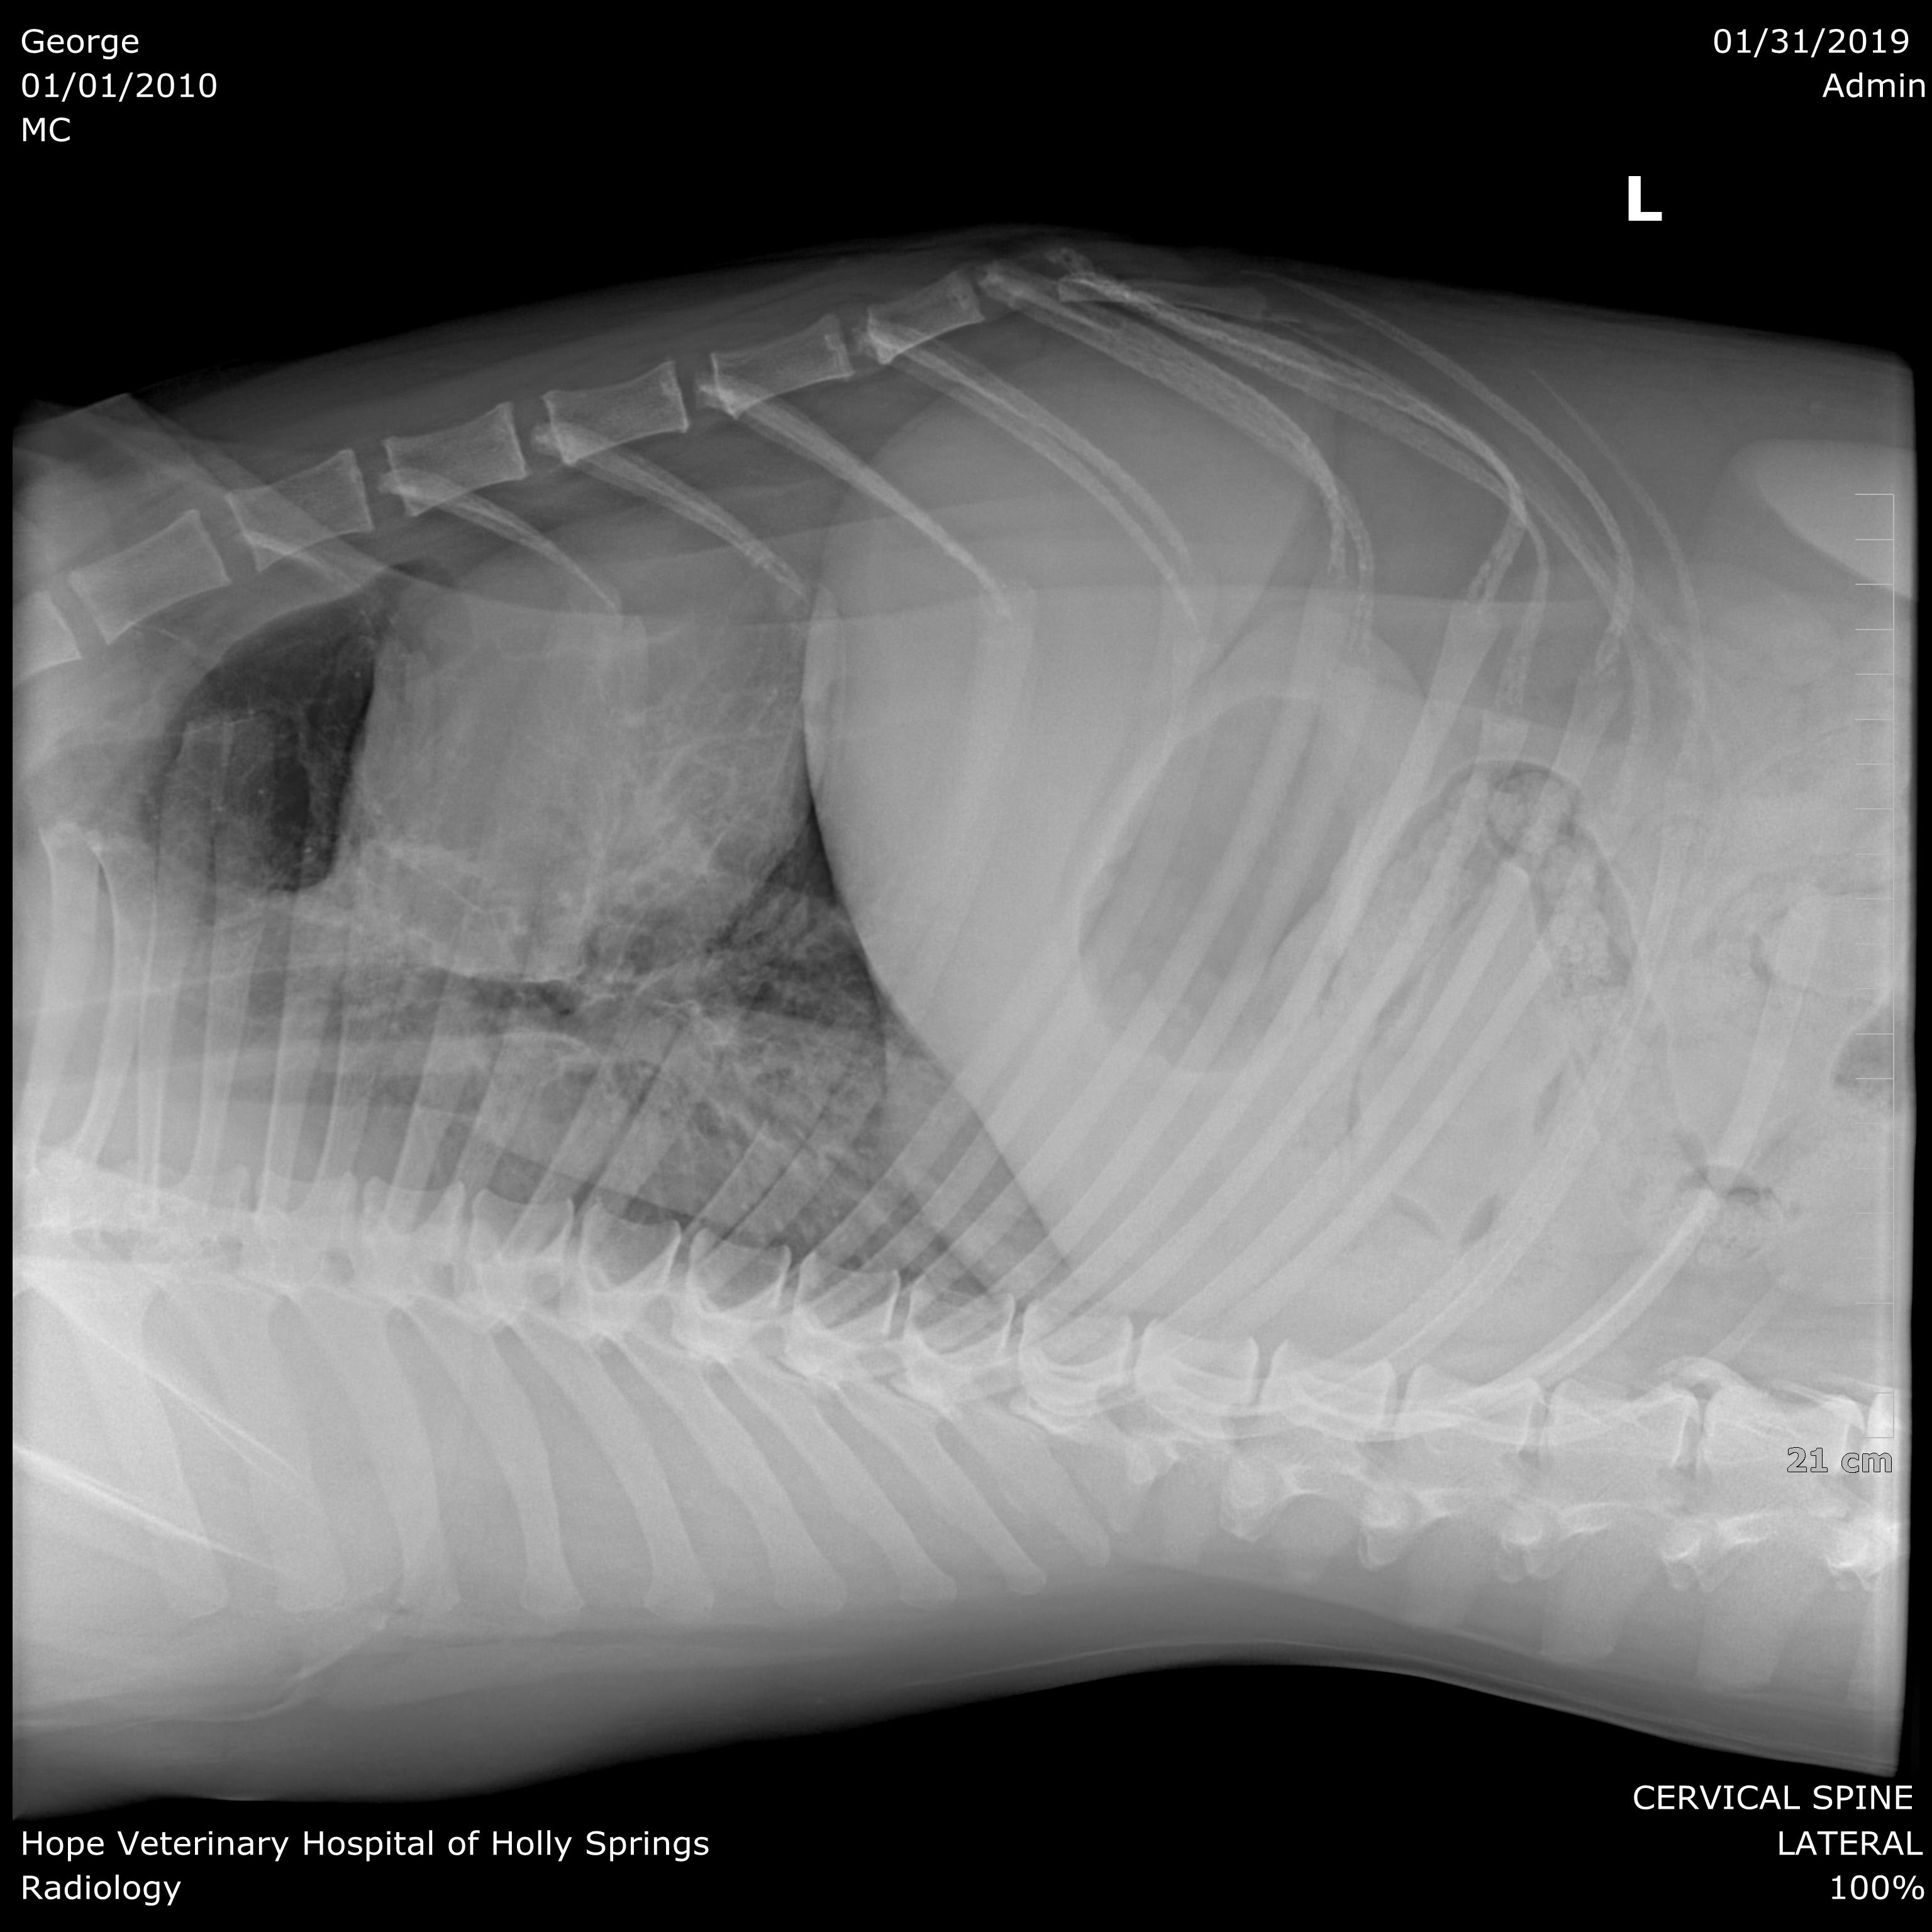

Pet's info: Dog | Mixed Breed Large (61lb +) | Male | neutered | 8 years and 9 months old | 83 lbs

We are looking for a second opinion. Do you see anything remarkable in these xrays?

Hello and welcome to Petco Pet Education Center, formerly Petcoach. Looking at x-rays that are not viewed with a proper screen can be very difficult, so it can be easy to miss things on these images. I can see the following: 1. The heart does NOT appear to be enlarged 2. The lungs have a slight increased opacity around the peri-hilar region (this can sometimes be associated with heart disease) 3. There is poor detail in the abdomen (this could be due to 'chest settings' and not actually 'real') 4. There is some discospondylosis present in the lumbar vertebrae (bridging between two vertebrae- likely inconsequential) 5. There is no sign of free fluid or free gas in the chest cavity 6. On the second image there is some gas in the esophagus, but this might be artifact of being sedated. 7. On the second image the lungs seem more 'white' then they should be, in the caudo-dorsal region. I recommend that if you are still unsure, have the x-rays sent to a radiologist specialist, as they will get a format they can better manipulate and give you better information about the lung parenchyma (tissue itself of the lungs) which is very hard to evaluate with the images you have provided. I don't see anything too remarkable in these x-rays. If you tell us what is clinically wrong with George we can look at the images again with his clinical picture in mind. Best of luck with George!